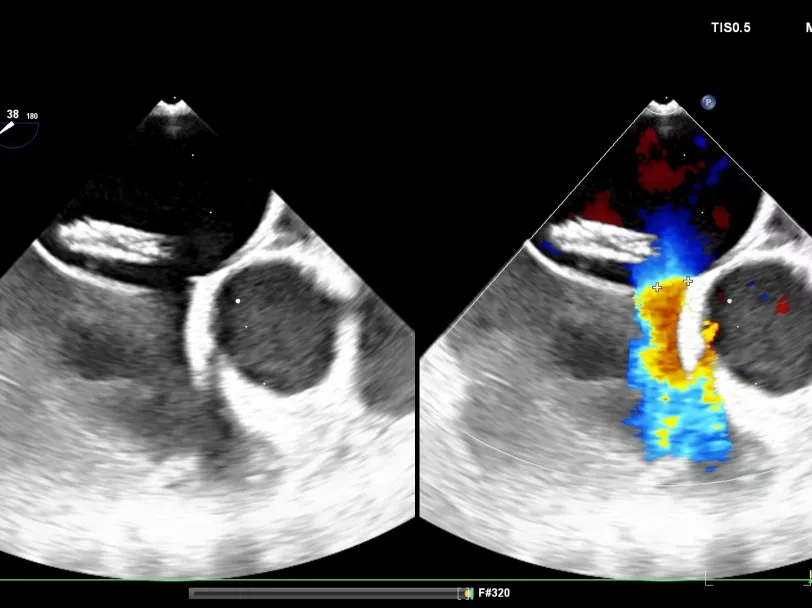

术中食道超声

经食道超声可见

第一个缺损8.06mm

第二个缺损5.63mm

术中超声:术中经食道超声可见有两个缺损,分别为8.06mm、5.63mm,和术前超声报告对比有所偏差,两缺损距离约8.48mm。